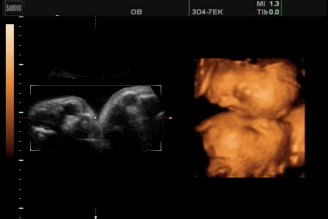

正常情况下一次完成,但是一次要看两个宝宝,需要的时间会长一点,并且两个人在一起会相互影响,所以会给操作者增加难度。为什么说正常情况下做一次即可呢?因为即使是单胎也有可能出现一些情况,比如宝宝不配合,看不清楚重要部位等,就只能再做一次,双胎一次看不清的概率会更大。

检查宝w宝的项目有哪些:NT、大排畸、小排畸、羊水穿刺等。但是像大排畸如果第一天没有时间安全看清楚,需要第二天补做的就不用再交钱啦,跟医生约好时间第二天直接去做就好了哈。

大排畸的最佳检查时间是20-24周,最迟不能超过28周。太晚了,胎儿活动受限,骨骼有了回声,身体的一些情况就看不出来了。

器官检查:头颈部、腹部、脊椎、胸部、四肢检查。确认有没有脑积水、脊柱裂、肢体畸形、先天心脏病等。

五官检查:鼻子、嘴巴,有没有兔唇现象。

大排畸并不能检查出胎儿所有畸形,像染色体异常,听力障碍、智力障碍、视力障碍等,也受宝宝体位、母体情况、羊水量等指标的影响,会存在有些部位看不清楚的情况。所以,不要错过每一次产检。